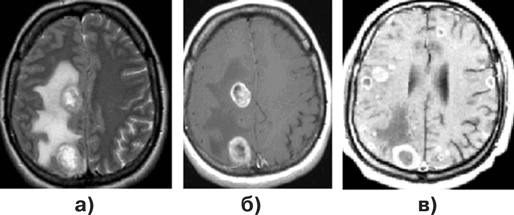

Диагноз подтверждается при МРТ, причем для визуализации небольших метастазов исследование целесообразно выполнять сразу с контрастированием препаратом гадолиния. Обычно метастазы выглядят как зоны повышенного сигнала как в Т1, так и Т2 режимах МРТ (рис. 1–3).

Рисунок 3. Множественные метастазы в головной мозг:

Наличие солитарного очага, выявленного при МРТ или КТ у больного диссеминированным раком, не является однозначным признаком метастатического поражения головного мозга. При обнаружении очага кольцевидной формы необходим дифференциальный диагноз с абсцессом, гематомой в стадии рассасывания, очагом демиелинизации и злокачественной глиомой, при отсутствии кольцевидного накопления контраста по периферии опухоли следует учитывать возможность наличия у больного энцефалитического очага, гранулемы, кровоизлияния, лучевого некроза. В сомнительных случаях показано исследование метаболитов в патологическом очаге при помощи МР-спектроскопии или ПЭТ, или стереотаксическая биопсия. Также стереотаксическая биопсия применяется при множественных очагах поражения с целью верификации гистологического диагноза.